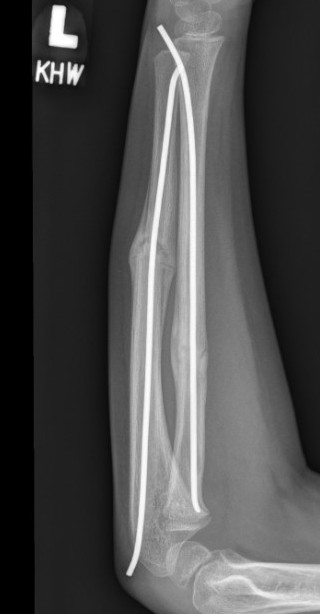

3. Intramedullary elastic nail

TENS technique

Technique

Radius (typically first as more difficult to reduce)

Entry point with awl 2 cm proximal to distal physis

1. Radial styloid / distal lateral entry

- ensure radial nerve / cephalic vein, 1st extensor compartment protected

2. Listers tubercle / dorsal entry

Elastic Nail size

60 - 70% of the intramedullary canal

Typically 1.5 - 2.5 mm

Fracture reduction

Avoid passing nails incorrectly multiple times as may cause compartment syndrome

Bend tip of elastic nail

May need small open reduction

Cut nail

Withdraw 1 cm, cut with endcutter, then advance

Ulna (usually reduced after radius fixation)

Entry point 2 cm distal to apophyseal plate

1. Proximal lateral

- avoids ulna nerve

3. Distal medial

Postoperative

Cast in supination to tighten interosseous membrane

Cast 6 weeks

Removal of TENS at 4 - 6 months once osseous union established